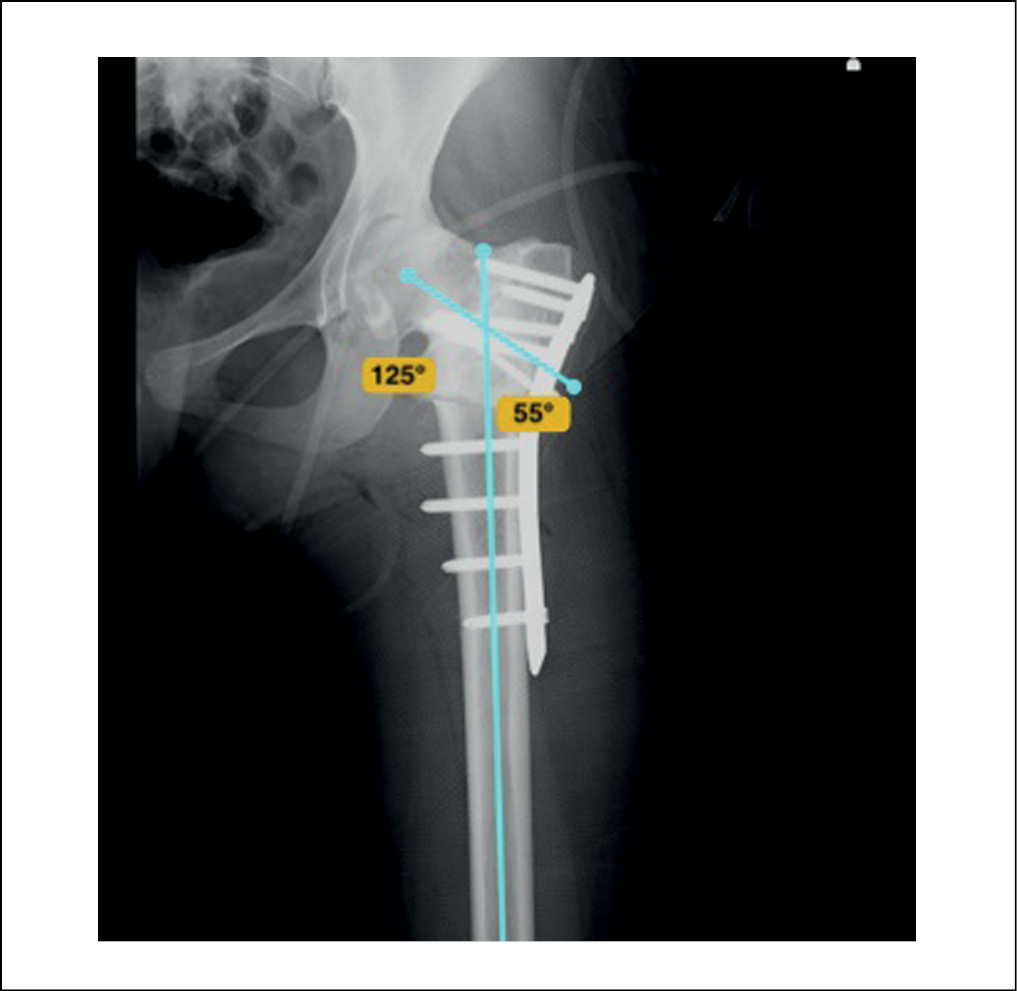

Пациентка госпитализирована в отделение травматологии и ортопедии №1 Клиник СамГМУ в плановом порядке на оперативное лечение. В качестве варианта оперативного вмешательства рассматривались остеотомия проксимального отдела бедренной кости и коррекция деформации в аппарате внешней фиксации, от чего пациентка отказалась. В качестве альтернативного варианта оперативного лечения выбрана деваризирующая корригирующая полуоткрытая-полузакрытая межвертельная остеотомия проксимального отдела левой бедренной кости с фиксацией пластиной и винтами. В результате оперативного вмешательства достигнуты стабильный остеосинтез, коррекция ШДУ до 125°, а также коррекция дефицита длины конечности до 1,0 см (рисунок 5).

Рисунок 5. Контрольная рентгенография левого тазобедренного сустава пациентки К., 2000 г.р., после выполнения корригирующей остеотомии проксимального отдела бедренной кости с фиксацией пластиной и винтами. Достигнута коррекция ШДУ до 125°. / Figure 5. Control radiography of the left hip joint of patient K., born in 2000, after corrective osteotomy of the proximal femur with fixation with a plate and screws. NSA correction up to 125° is achieved.

Интраоперационно при выполнении остеотомии и проведении винтов через зону реорганизации костного гомотрансплантата отмечалась состоятельность регенерата, признаки анатомичной перестройки трансплантата с формированием трабекулярной структуры, сходной с нативной костной тканью. Описанные качества реорганизованной костной ткани позволили выполнить полноценную корригирующую остеотомию и стабильный состоятельный остеосинтез. Левая нижняя конечность иммобилизирована в полимерной кокситной повязке на 8 недель. В послеоперационном периоде проведена антибактериальная, симптоматическая, обезболивающая терапия.